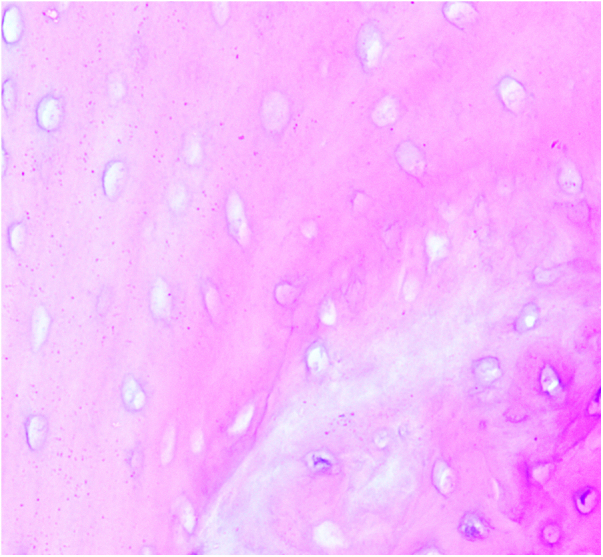

本研究旨在探讨自然杀伤细胞(NK)在股骨头骨坏死(ONFH)中RANKL/RANK/OPG通路中的作用。将C57小鼠分为对照组、观察组(每组10只)和实验组(4只NK细胞敲除小鼠)。采用脂多糖联合甲基强的松龙给药8周,建立激素性股骨头坏死模型。观察组患者皮下注射等量生理盐水。8周后取小鼠外周血,死后取双侧股骨头标本。采用PCR和ELISA技术检测ONFH小鼠外周血和关节液中NK细胞、OPG、RANK、RANKL的表达水平,并与对照组进行比较。与对照组相比,实验组外周血和关节液中NK细胞数量增加。OPG表达下调,RANK和RANKL显著上调,导致成熟破骨细胞数量明显增加。在ONFH患者中,NK细胞上调TNF-α和RANKL,下调IFN-γ和OPG,促进破骨细胞成熟,破坏骨平衡,加速股骨头坏死塌陷,最终加速股骨头坏死的进展。

This study aimed to investigate the role of natural killer (NK) cells in the RANKL/RANK/OPG pathway in osteonecrosis of the femoral head (ONFH). C57 mice were categorized into a control group, an observation group (10 mice each), and an experimental group comprising 4 NK cell knockout mice. A hormone-induced femoral head necrosis model was created by administering lipopolysaccharide combined with methylprednisolone for 8 weeks to the experimental and control groups. The observation group received subcutaneous injections of an equal amount of normal saline. After 8 weeks, peripheral blood was collected from the mice, and bilateral femoral head specimens were obtained post-mortem. Expression levels of NK cells, OPG, RANK, and RANKL in the peripheral blood and joint fluid of ONFH mice were determined using PCR and ELISA techniques, and compared with the control group. The experimental group exhibited an increased number of NK cells in the peripheral blood and joint fluid compared to the control group. OPG expression was downregulated, while RANK and RANKL were significantly upregulated, resulting in a marked increase in the number of mature osteoclasts. In ONFH patients, NK cells were found to upregulate TNF-α and RANKL, downregulate IFN-γ and OPG, promote osteoclast maturation, disrupt bone balance, accelerate femoral head necrosis collapse, and ultimately hasten the progression of femoral head necrosis.